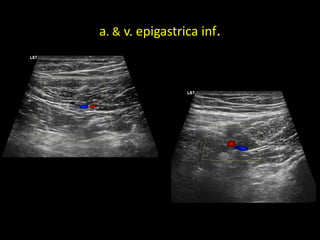

a. & v. epigastrica inf.

a. & v.epigastrica inf.